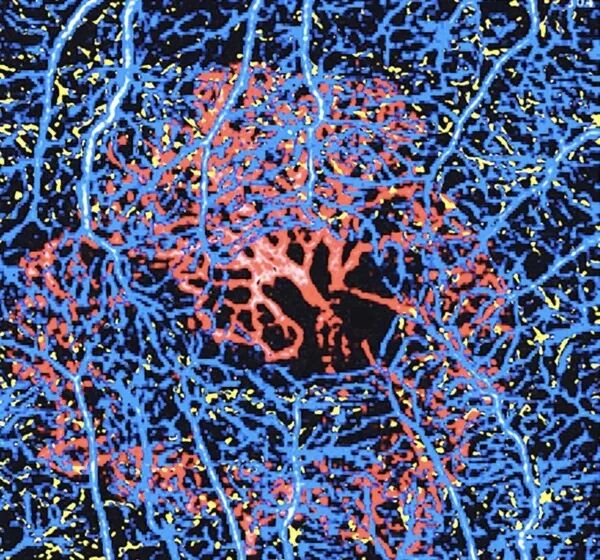

L’OCT-Angiographie ou OCTA est une angiographie combinée à la tomographie par cohérence optique (OCT), elle ne nécessite aucune injection de produit de contraste. Cette technologie relativement récente a permis de découvrir de nouvelles pathologies, de détecter de façon précoce infra clinique, des maculopathies naissantes.